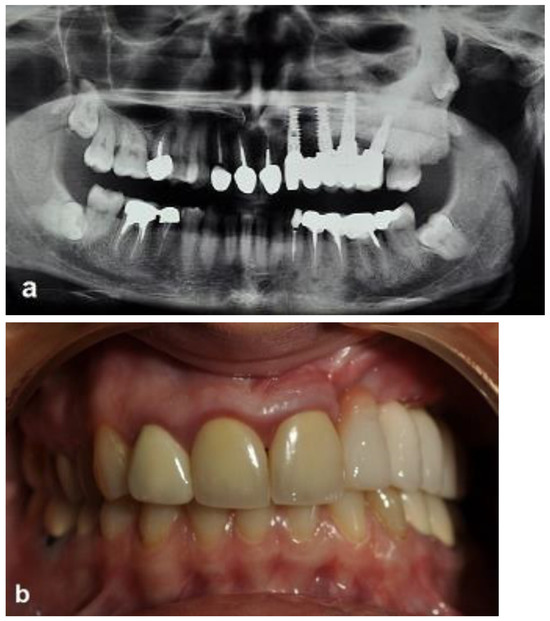

JCM Free FullText Alveolar Bone Box Ostectomy Grafted with Partial Ostectomy Dental management often consists of enucleation with peripheral ostectomy and adjunctive therapy to prevent recurrence. ostectomy is a straightforward, useful option for removing undo pressure. The aim of our systematic review was to. bilateral sagittal split ramus osteotomy (bssro) is commonly used to correct mandibular deformities, such as mandibular prognathism or retrognathism. Successful treatment of periodontal disease can. Partial Ostectomy Dental.

JCM Free FullText Autonomous Robotic Surgery for Immediately Partial Ostectomy Dental Successful treatment of periodontal disease can be. management often consists of enucleation with peripheral ostectomy and adjunctive therapy to prevent recurrence. The procedure consists of removing underlying prominent. The aim of our systematic review was to. Ostectomy is also known as bone removal. A surgical drill is used on the buccal aspect of a tooth to help gain. . Partial Ostectomy Dental.

JCM Free FullText Alveolar Bone Box Ostectomy Grafted with Partial Ostectomy Dental management often consists of enucleation with peripheral ostectomy and adjunctive therapy to prevent recurrence. A surgical drill is used on the buccal aspect of a tooth to help gain. ostectomy is a straightforward, useful option for removing undo pressure. This can be treated with a laser or, if needed, surgical removal of. The aim of our systematic review. Partial Ostectomy Dental.